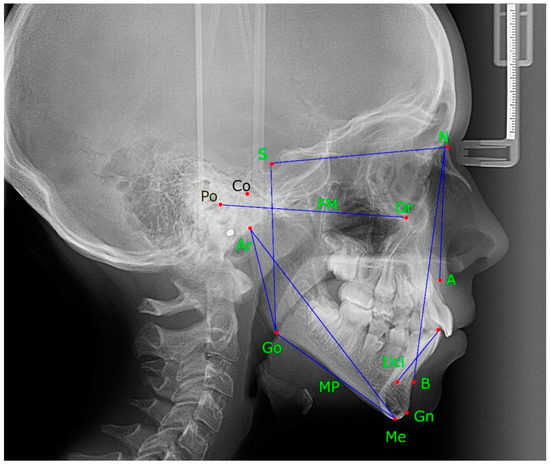

| Nebbe, 1998 [25] | to test the hypothesis of no difference in facial cephalometric measurements in adolescents with DD | study group: bilateral DD 17 teenage girls, 13.65 years on average Control group: ND position 17 teenage girls, 13.53 years on average | MRI | study group: lower overall posterior height (S-Go) reduced mandibular ramus length (Co-Go, Ar-Go) shortened posterior facial height (S-Ar) increase in the distance from S-N to the palatal plane increase in the distance from S-N to a line tangent to the inferior border of the mandible’s body posterior displacement of Gn related to anterior structures of the face posterior rotation of the mandible Control group: higher mandibular lateral displacement inclined frontal occlusal plane | lateral cephalogram | mean differences (95% CI): Ar-Go (mm) 4.18 (0.69–7.68); Ar-Me 4.33 (mm) (−0.01–8.68); Ar-Go-Me (degrees) 0.46 (−4.18–3.27); FH/MP 3.80 (degrees) (−8.02–0.42); S-Go (mm) 5.57 (1.96–9.18); N-Me (mm) 1.07 (−5.54–3.40) | bilateral DD: posterior vertical facial height diminished; Juvenile disc position aberrations are not within the range of typical physiologic diversity. |

| Shi, 2010 [27] | to evaluate the relationship between partial DD and mandibular dysplasia | 46 female adolescents aged 10.1–12.8 years. DD group (n = 26), ND group (n = 20) | MRI | the displaced group exhibited a reduced length of the mandible (Go-Po), sharper mandible plane (MP/FH), and steep mandible inclination (Ar-Go-Me) | lateral cephalograms | DD vs. ND: SNA(°) 79.31 ± 3.40 vs. 80.15 ± 4.79, p = 0.489; SNB(°) 74.31 3.06 vs. 75.25 5.09, p = 0.440; ANB(°) 6 ± 1.45 vs. 6 ± 1.02, p = 1; Ar-Go(mm) 45.42 ± 4.59 vs. 47.75 ± 6.50, p = 0.162; Ar-Me(mm) 95.73 ± 4.68 vs. 99.05 ± 6.95, p = 0.060; Go-Po(mm) 69.00 ± 3.96 vs. 72.00 ± 3.54, p = 0.011 *; Ar-Go-Me (°) 118.77 ± 5.03 vs. 115.75 ± 2.78, p = 0.020 *; MP/FH (°) 31.23 ± 3.85 vs. 26.80 ± 5.54, p = 0.003; S-Go(mm) 74.50 ± 3.26 vs. 76.50 ± 5.57, p = 0.134; N-Me(mm) 116.12 ± 4.22 vs. 116.30 ± 4.96, p = 0.892 | partial DD may be related to horizontal jaw impairments but not longitudinal abnormalities |

| Bastos, 2012 [24] | to evaluate differences between the cephalometric variables for facial growth patterns in children and adolescents with articular TMD and control group | Experimental group 30 patients with articular TMD. Control group: 30 volunteers without TMD, matched | RDC/ TMD | the analysis of the post-peak of pubertal growth spurt showed that the experimental group had mean values for SNA and SNB angles decreased, and the facial axis angle (SN.Gn) and lower incisor inclination (1-NB) increased with the mean values found in the control group, revealing statistically significant differences | lateral cephalograms | DD vs. ND:Pre-peak: S.N.A (°) 82.05 ± 3.03 vs. 81.39 ± 4.34, p = 0.611; S.N.B (°) 4.30 ± 1.91 vs. 3.98 ± 4.63, p = 0.799; A.N.B (°) 4.3 ± 1.91 vs. 3.98 ± 4.63, p = 0.799; Ar-Go (mm) 39.22 ± 3.86 vs. 39.46 ± 3.50, p = 0.853; Ar.Go.Me (°) 129.66 ± 6.75 vs. 126.15 ± 5.37, p = 0.104; S-Go (mm) 68.25 ± 6.10 vs. 67.23 ± 5.68, p = 0.619; N-Me (mm) 110.40 ± 7.96 vs. 110.24 ± 7.69, p = 0.952; post-peak: S.N.A (°) 78.25 ± 3.55 vs. 82.90 ± 4.53, p = 0.008; S.N.B (°) 74.69 ± 3.63 vs. 79.26 ± 4.75, p = 0.011; A.N.B (°) 3.55 ± 2.98 vs. 3.71 ± 2.89, p = 0.891; Ar-Go (mm) 42.18 ± 3.53 vs. 43.12 ± 3.99, p = 0.532; Ar.Go.Me (°) 125.76 ± 5.59 vs. 128.02 ± 4.42, p = 0.265; S-Go (mm) 73.42 ± 6.42 vs. 72.99 ± 4.36, p = 0.842; N-Me (mm) 121.26 ± 9.21 vs. 115.37 ± 7.58, p = 0.088 | changes in morphometric parameters were detected in youngsters with joint TMD |